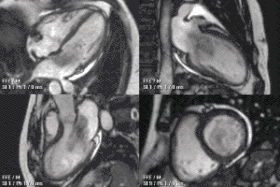

Congenital heart defects are the most common type of major birth defect. Accurate diagnosis is essential for the development of appropriate treatment plans. CMR can provide comprehensive information about the nature of congenital hearts defects in a safe fashion without using x-rays or entering the body. It is rarely used as the first or sole diagnostic test for congenital heart disease.

Rather, it is typically used in concert with other diagnostic techniques. In general, the clinical reasons for a CMR examination fall into one or more of the following categories: (1) when echocardiography (cardiac ultrasound) cannot provide sufficient diagnostic information, (2) as an alternative to diagnostic cardiac catheterization which involve risks including x-ray radiation exposure, (3) to obtain diagnostic information for which CMR offers unique advantages such as blood flow measurement or identification of cardiac masses, and (4) when clinical assessment and other diagnostic tests are inconsistent. Examples of conditions in which CMR is often used include tetralogy of Fallot, transposition of the great arteries, coarctation of the aorta, single ventricle heart disease, abnormalities of the pulmonary veins, atrial septal defect, connective tissue diseases such as Marfan syndrome, vascular rings, abnormal origins of the coronary arteries, and cardiac tumors.

Atrial septal defect with dilation of the right ventricle by CMR

Partial Anomalous Pulmonary Venous Drainage by CMR